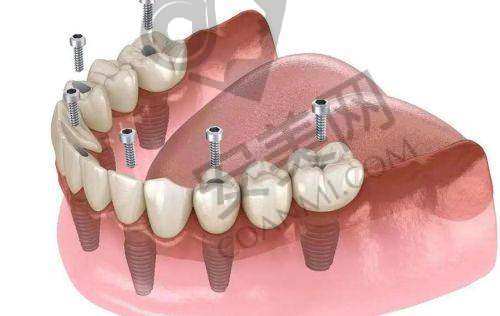

all - on - 4 半口种植牙是一种精良的牙齿种植技术。它通过在牙槽骨内植入四颗种植体,然后利用这四颗种植体来支撑半口牙桥,从而实现半口牙齿的修复。与传统的种植牙技术相比,all - on - 4 半口种植牙具有许多优势。

首先,手术时间短。传统的半口种植牙可能需要植入更多的种植体,手术过程复杂,时间较长。而 all - on - 4 半口种植牙只需要植入四颗种植体,大大缩短了手术时间,减少了患者的痛苦。其次,费用相对较低。由于减少了种植体的使用数量,all - on - 4 半口种植牙的费用相对传统种植牙更为亲民。末尾,稳定性好。四颗种植体呈特定的角度植入牙槽骨内,能够提供足够的支撑力,使牙桥更加稳定,咀嚼功能也能得到良好的修复。

此外,all - on - 4 半口种植牙还具有美观自然的成效。种植后的牙齿与天然牙齿非常相似,几乎看不出是人工种植的。而且,它的使用寿命也比较长,只要患者做好日常的口腔护理,就可以长期使用。